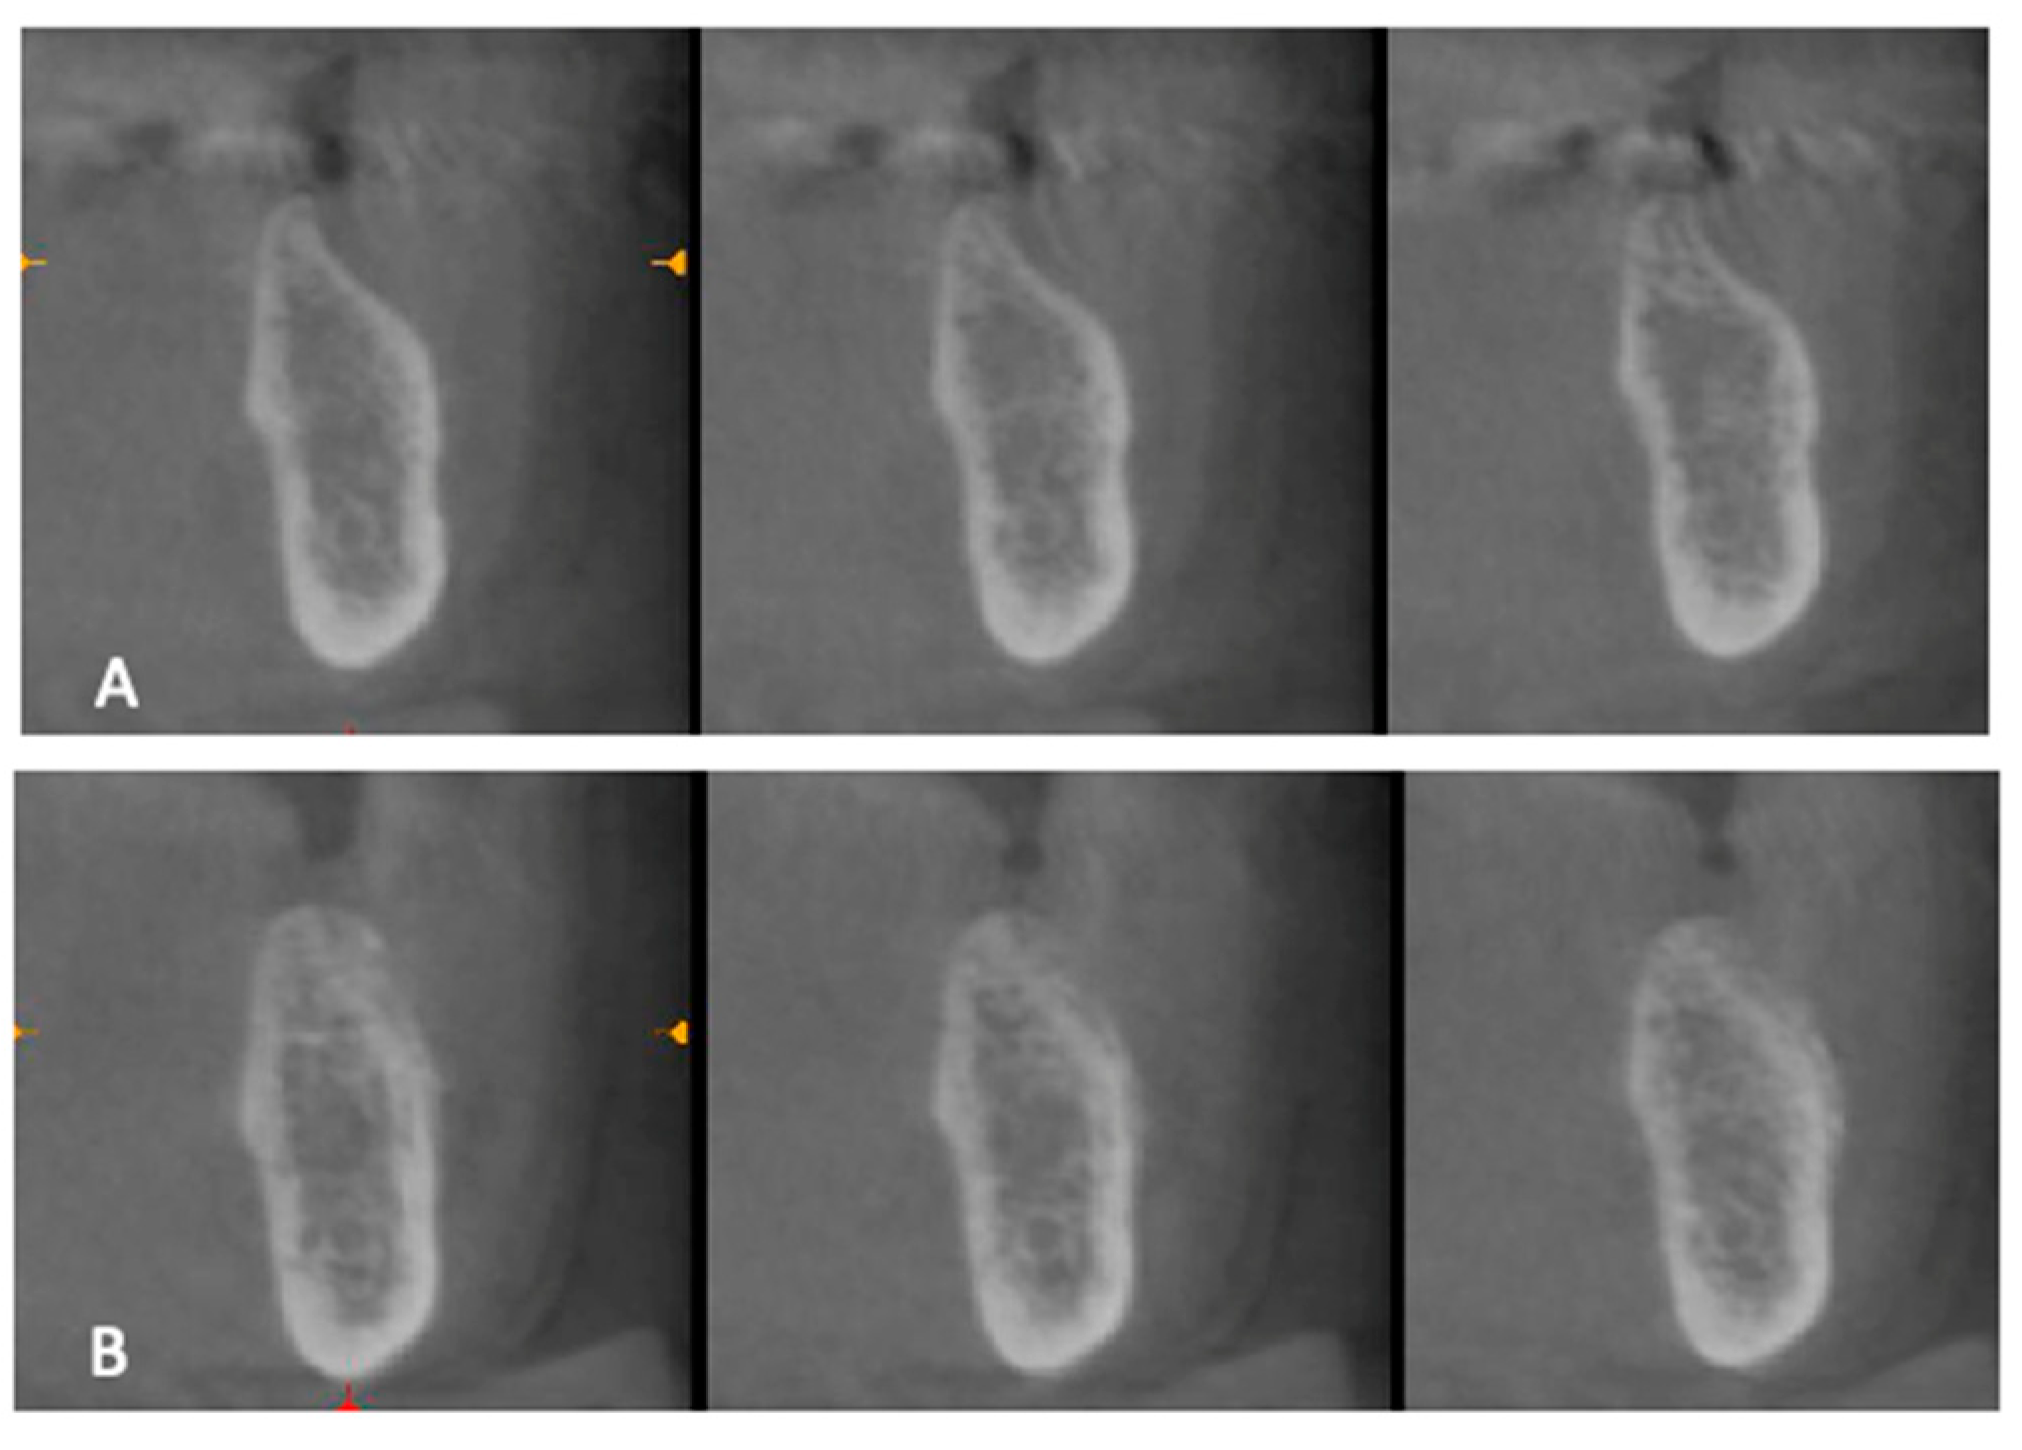

2.4. Preoperative Work-Up

2.5. Surgical Procedures and Follow-Up